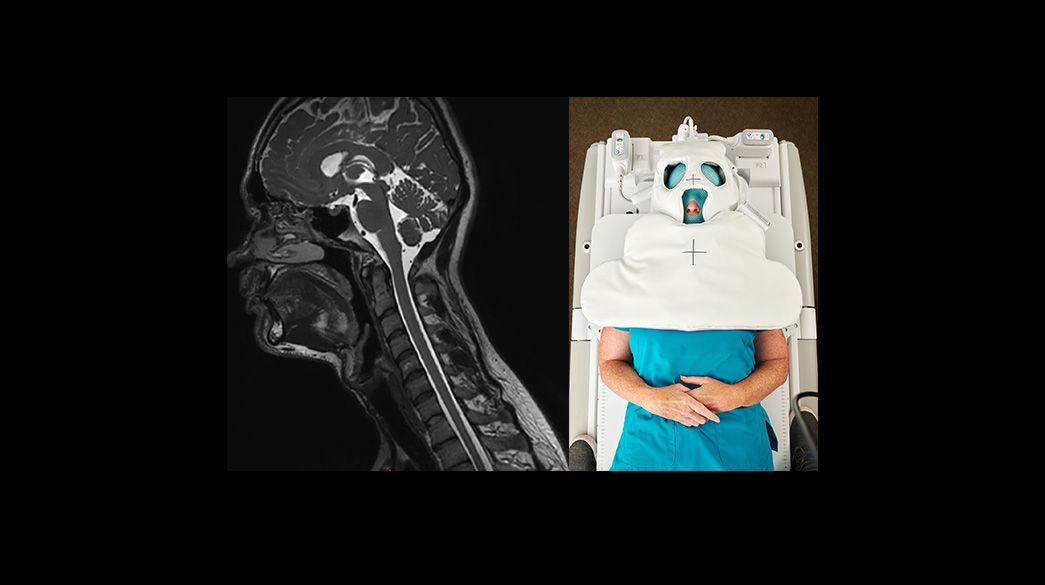

Oncology MR imaging techniques to capture anatomical and morphological data with robust tissue contrast, motion-insensitive and high temporal and spatial resolution for oncological assessment.

AIR-RT-Coils-suite1040-x-585

With overlapping, ultra-light, flexible coil elements at their heart, AIR™ Coils deliver an MRI experience that gets closer to your patient.